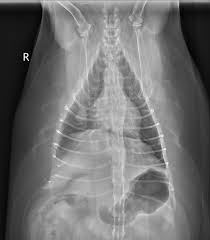

So, if a dog that first got cancer in their mouth for instance, or in their bones, they risk the chance of it metastasizing through the bloodstream to the lungs. For many dogs, the recommended treatment is surgery. Metastasis is rare in dogs with axial tumors, except for osteosarcoma of the ribs, scapula or pelvis.1 the diagnosis of osteosarcoma with metastatic disease is historically associated with a First of all, surgical removal is the most straightforward way of eliminating the cancerous cells because it is a way of literally removing the cancerous lung tumor. Your dog must be fit for surgery and undergo this procedure with an oncologist. Metastatic lung cancer can be treated with radiation or chemotherapy. Holistic vets evaluate dog cancer supplements. Dogs generally tolerate this surgery well and are discharged soon after the procedure. Metastatic lung cancer originates in other parts of the body such as a leg bone, the mouth, or the thyroid gland, but has spread to the lung through the bloodstream. The second kind of lung cancer in dogs is called metastatic lung cancer, which means the cancer originated somewhere else in the body, but has spread to the lung. Radiation therapy is sometimes used for the treatment of lung cancer in dogs depending upon the proximity of the lung tumor to the heart. Generally, this smaller number of metastases occurs when the primary cancer is an osteosarcoma. They can be detected on chest radiographs or computed tomography (ct) scanning.

If you discovered that your dog or cat has lung metastasis before amputation surgery, you may want to ask your veterinarian about bisphosphonates and palladia, two pet cancer therapies to reduce pain, that are useful when amputation is not an option. Generally, this smaller number of metastases occurs when the primary cancer is an osteosarcoma. They can be detected on chest radiographs or computed tomography (ct) scanning. Computed tomography (ct scan) can be performed to identify some of these lung tumors. Fewer ingredients in a properly balanced fresh food diet = better nutrition and a stronger immune system.

In most cases, radiation therapy may be used to help reduce the size of the tumor and destroy the cancerous cells. Surgery for canine lung cancer surgery is by far the mainstay of treatment for dogs with lung carcinoma or histiocytic sarcoma of the lungs, especially with a single mass. A complete medical history and a physical exam are important because it will establish a list of possible diagnoses. The lung is the most common location for metastatic osteosarcoma. So, if a dog that first got cancer in their mouth for instance, or in their bones, they risk the chance of it metastasizing through the bloodstream to the lungs. All these herbal formulas can safely be used with chemotherapy or radiation with the exception of artemisinin. Older dogs are also more often diagnosed with lung cancer. They can be detected on chest radiographs or computed tomography (ct) scanning. A 2012 study looked at turkey tail mushrooms in treating dogs with hemangiosarcoma. The average survival is closer to 8 months for dogs with big tumors, and 2 months if there is metastasis. Treatment for lung cancer in dogs if your dog is diagnosed with lung cancer, surgery to remove the portion of the lung where the tumor is located may be recommended. Most lung tumors are malignant carcinomas and hemangiosarcoma. These are some of the principles i follow for my cancer patients.